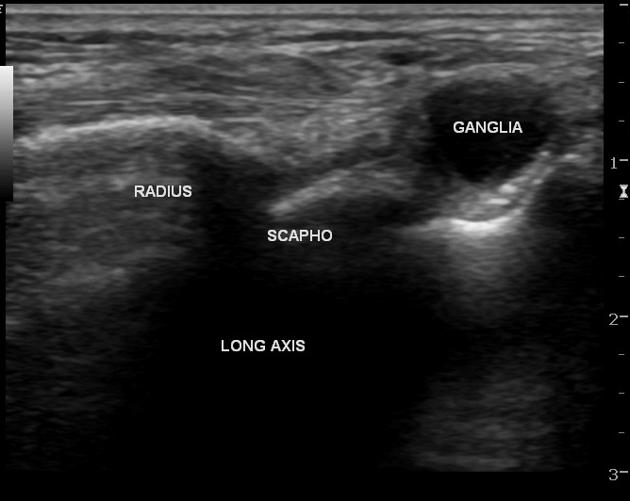

초음파 검사상 관절낭에서 시작한 물혹 @Radiopaedia

위 초음파 이미지처럼

관절에서 시작된 물혹은

관절 염증이 없어져야

결절종이 재발하지 않습니다.